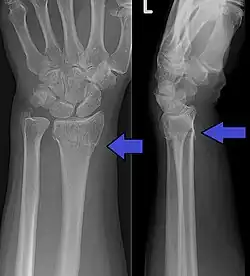

A Colles fracture as seen on X-ray: It is a type of distal radius fracture.

A distal radius fracture, also known as wrist fracture, is a break of the part of the radius bone which is close to the wrist.[1] Symptoms include pain, bruising, and rapid-onset swelling.[1] The ulna bone may also be broken.[1]

In younger people, these fractures typically occur during sports or a motor vehicle collision.[2] In older people, the most common cause is falling on an outstretched hand.[2] Specific types include Colles, Smith, Barton, and Chauffeur's fractures.[2] The diagnosis is generally suspected based on symptoms and confirmed with X-rays.[1]